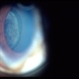

- Ciliary Body Melanoma

- Jason S. Calhoun, Department of Ophthalmology, Mayo Clinic Jacksonville, Florida

- Imaging device

- Photo slit lamp biomicroscope

- 71-year-old male who was recently diagnosed with a large ciliary body melanoma that is pushing into the anterior chamber of the left eye. Patient is going to proceed with proton therapy.